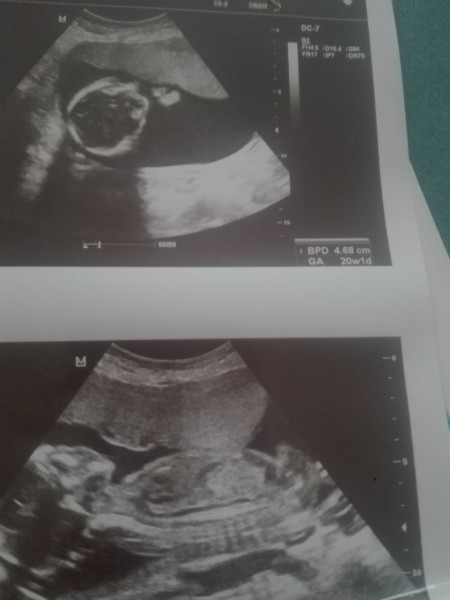

Bebişimin cinsiyeti ne acaba tahmin edebilirmisiniz

Doktor soyledide sizdende duymak istedim

19 haftalik

Yok doktor belli degil daha dedi ondan atmak istedim

%50 kız bu

Kiza benziyor dedi ama tam kesin birseyde soyliyemem dedi . Bide ilk gebeligim

doktor ne dedi canım kız gibi sanki

Bacak arasindaki çikinti var ben erkek diye dusunuyorum hayirlisi artk